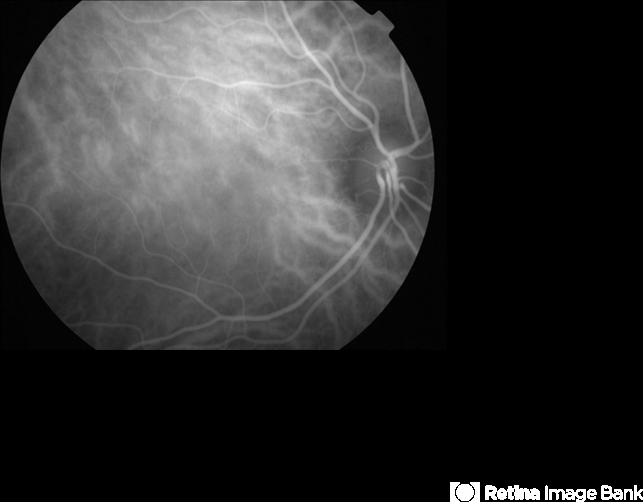

- A 17-year-old healthy woman noticed a pacman-shaped scotoma in her temporal right vision. Acuity measured 20/20 and color vision measured 11/11. Indocyanine angiography was unremarkable.